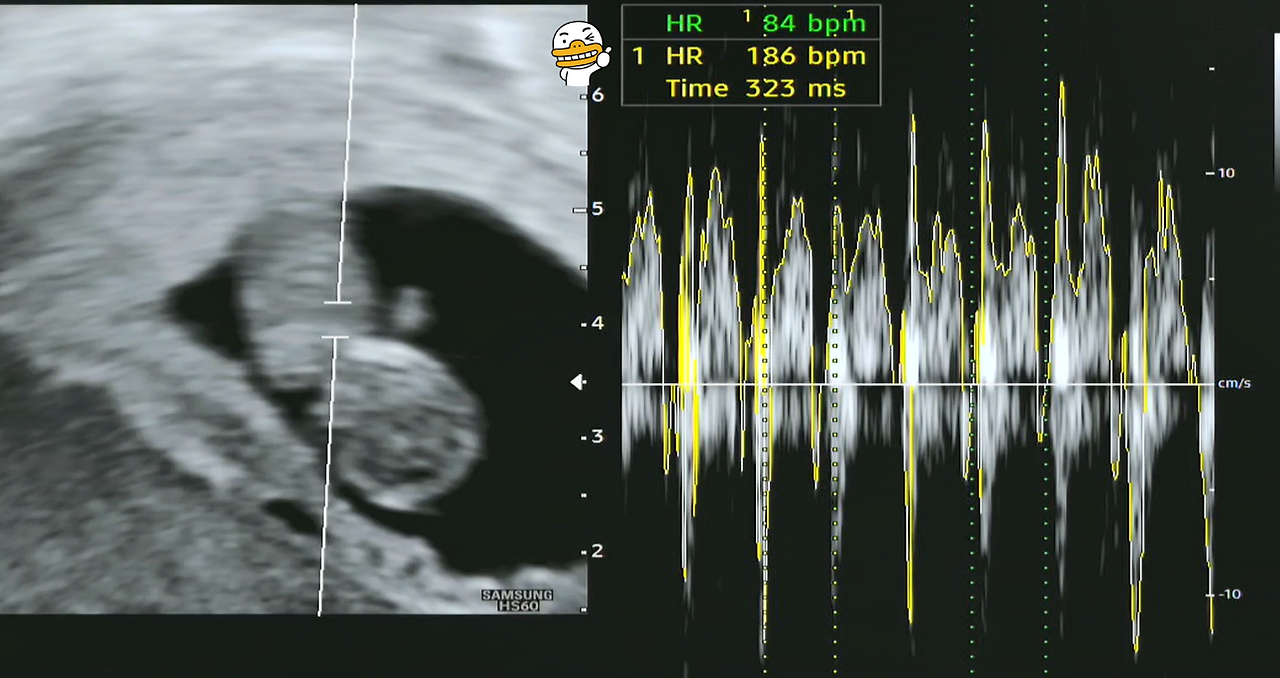

인터넷을 보니 9주 차 태아의 크기는 머리부터 아래까지 약 22mm 정도로 자란다고 합니다. 손과 발도 발달하고 있지만 가장 중요한 것은 아기의 심장, 뇌, 폐, 신장, 장 등 모든 주요 내부 장기가 발달하는 시점이라고 하네요. 그리고 심장 박동은 180 bpm 정도로 매우 빠르게 뛴다고 합니다. 대략 성인의 심장 박동수의 2~3배가 되는 수치네요.

제가 우리 '팡팡이'의 초음파 사진을 분석(?)해보니, 크기는 22.8mm이고 심장 박동수도 186 bpm으로 지극히 정상으로 보입니다.

9주차 태아 심장 bpm.png

[왼쪽 - 심장 박동수(186 bpm), 오른쪽 - 태아 크기(22.8mm)]